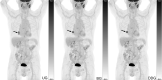

Background: This study examines the clinical feasibility and impact of implementing a fully automated whole-body PET protocol with data-driven respiratory gating in patients with a broad range of oncological and non-oncological pathologies 592 FDG PET/CT patients were prospectively included. 200 patients with lesions in the torso were selected for further analysis, and ungated (UG), belt gated (BG) and data-driven gating (DDG) images were reconstructed. All images were reconstructed using the same data and without prolonged acquisition time for gated images. Images were quantitatively analysed for lesion uptake and metabolic volume, complemented by a qualitative analysis of visual lesion detection. In addition, the impact of gating on treatment response evaluation was evaluated in 23 patients with malignant lymphoma.

Results: Placement of the belt needed for BG was associated with problems in 27% of the BG scans, whereas no issues were reported using DDG imaging. For lesion quantification, DDG and BG images had significantly greater SUV values and smaller volumes than UG. The physicians reported notable image blurring in 44% of the UG images that was problematic for clinical evaluation in 4.5% of cases.

Conclusion: Respiratory motion compensation using DDG is readily integrated into clinical routine and produce images with more accurate and significantly greater SUV values and smaller metabolic volumes. In our broad cohort of patients, the physicians overwhelmingly preferred gated over ungated images, with a slight preference for DDG images. However, even in patients with malignant disease in the torso, no additional diagnostic information was obtained by the gated images that could not be derived from the ungated images.